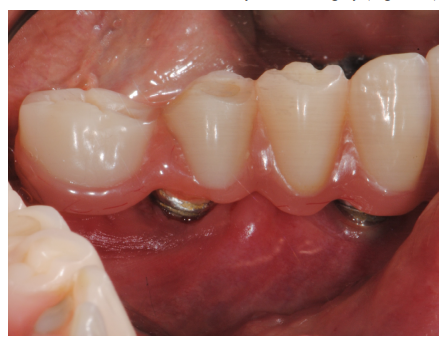

The condition of the soft tissues one year after surgery (Figure 45).

Figure 45